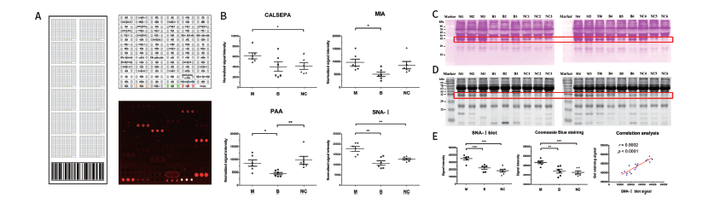

》以GA-Lectin 70 芯片的70种凝集素检测结果为例

如芯片扫描图所示,BANLEC、BC2L-A、CALSEPA、GNA、HHA、NPA、PA-IIL和PALA凝集素与生物素标记的HRP孵育后呈强荧光信号。已知这八种凝集素可以和甘露糖进行特异性结合,且后续分别以梯度增加HRP/甘露糖浓度进行实验,结果显示,结合的荧光信号都随浓度的增加而减弱,进一步表明HRP蛋白中含有甘露糖结构(与芯片上的凝集素进行特异性结合)。另外, AAL和RS-FUC两种凝集素(与岩藻糖特异性结合)也显示出与HRP的强相互作用,表明HRP发生岩藻糖基化。

经典案例2:糖蛋白标志物的发现:儿童肺炎鉴别诊断

该研究的论文作者有多名来自华盈生物研发团队,成功应用了华盈生物新建立的凝集素芯片-标志物研发方案,综合了蛋白芯片与质谱两种蛋白组学技术,为复杂疾病的临床标志物开发提供了新的研究思路,具有借鉴意义。

[5].Yang L, et al. Lectin Microarray Combined with Mass Spectrometry Identifies Haptoglobin-Related Protein (HPR) as a Potential Serologic Biomarker for Separating Nonbacterial Pneumonia from Bacterial Pneumonia in Childhood. Proteomics Clin Appl. 2018: e1800030. (上海儿童医学中心)